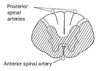

Spinal cord lesions: Complete occlusion of the anterior spinal artery What areas are affected? What are the Sx?

Spares dorsal columns and tract of Lissauer; upper throacic ASA territory is a watershed area, as artery of Adamkiewicz supplies ASA below ~T8

Spares dorsal columns and tract of Lissauer; upper throacic ASA territory is a watershed area, as artery of Adamkiewicz supplies ASA below ~T8 What disease is associated with this?

Complete occlusion of the anterior spinal artery